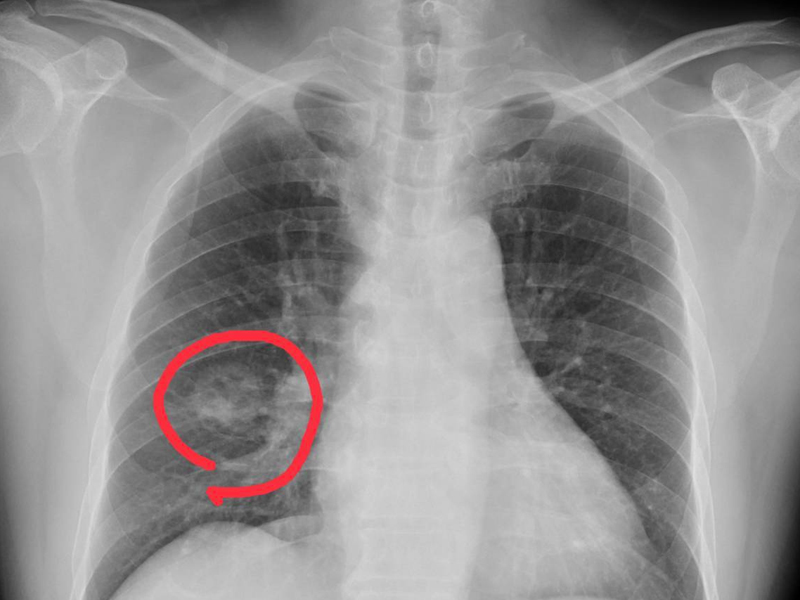

癌症,又稱惡性腫瘤,是由異常細胞無限制生長並擴散至身體其他部位所引發的疾病,可能干擾器官正常功能,嚴重時導致死亡。根據香港癌症資料統計中心 2022 年數據,本港五大常見癌症依次為肺癌、乳腺癌、大腸癌、前列腺癌及肝癌。專家強調,早期發現與及時治療可顯著提高治癒率,採取健康生活方式則能有效降低患癌風險。 癌症風險因素 可控與不可控並存 癌症風險因素分為不可控及可控兩類。不可控因素包括年齡、性別及家族癌症史;可控因素則涵蓋生活習慣與環境影響。超重及肥胖增加肝癌、大腸癌、乳癌等多種癌症風險;缺乏體能活動亦提升逾十種癌症的發生機率。不健康飲食,如過量紅肉、加工肉類或醃製食品,與大腸癌等疾病相關。吸煙、飲酒及過量紫外線暴露分別為肺癌、肝癌及皮膚癌的主要誘因。此外,環境污染、職業致癌物接觸及病毒感染(如乙型肝炎病毒、人類乳頭瘤病毒)亦是重要風險。專家建議,改善生活方式可顯著降低可控風險。 預防癌症 健康生活為關鍵 預防癌症需從多方面入手,包括維持體重指數 18.5 至 22.9 及健康腰圍(男性少於 90 厘米,女性少於 80 厘米),每周進行至少 150 分鐘中等強度帶氧運動,採取均衡飲食,增加蔬果攝取並減少紅肉及加工食品。戒煙、避免二手煙及酒精,減少紫外線暴露及致癌物接觸亦至關重要。接種乙型肝炎及人類乳頭瘤病毒疫苗,採取安全性行為,以及慢性乙型肝炎患者定期檢查,均有助降低患癌風險。專家強調,健康生活習慣結合疫苗預防可有效減少癌症發生。 早期警號與篩查 助及時發現 癌症早期症狀常不明顯,易與其他疾病混淆。專家提醒,長者應留意體重無故下降、胃口減退、持續疲倦,或異常症狀如大小便帶血、身體腫塊、陰道異常出血、痰中帶血、持續咳嗽、吞嚥困難或皮膚潰瘍等,及早求醫。癌症篩查可在無症狀時檢測潛在風險,政府已推出子宮頸普查計劃及大腸癌篩查計劃,旨在早期發現並提高治療成效。專家呼籲,公眾應積極參與篩查,並關注身體變化以把握治療時機。 |